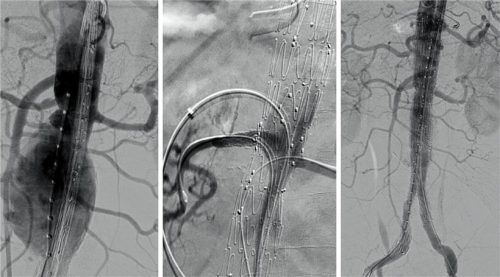

Ein Aneurysma vor, während und nach der Operation in Wasserburg. Fotos Romed Wasserburg

Wasserburg – 25 Jahre lang wusste Elmar R. (67), dass er ein Aneurysma im Bauchraum hat. Ein Zufallsbefund bei einem CT wegen Rückenbeschwerden. Jährlich ging es danach zur Kontrolle, die Ausweitung der Schlagader blieb relativ konstant auf einem Niveau von etwa 3,5 Zentimetern Durchmesser, berichte